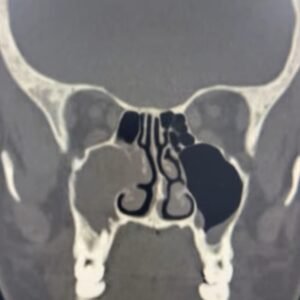

Anatomia cirúrgica e radiológica dos seios paranasais

Sinusotomias Maxilar, Etmoidal, Esfenoidal, Frontal

O Curso Endobrasília chega à sua terceira edição, consolidado como uma das principais imersões em cirurgia endoscópica nasal do país. Sempre muito bem avaliado pelos alunos, destaca-se pela combinação de conteúdo teórico de excelência, professores altamente dedicados e treinamento prático personalizado, proporcionando uma experiência completa e transformadora para otorrinolaringologistas e residentes.

No módulo teórico, os participantes terão acesso a aulas ministradas por especialistas reconhecidos, abordando técnicas cirúrgicas atualizadas, dicas fundamentais e estratégias para identificação segura dos reparos anatômicos essenciais. Essa base sólida prepara o aluno para executar as intervenções com segurança, precisão e maior confiança.